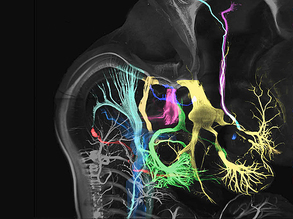

Looking Inside